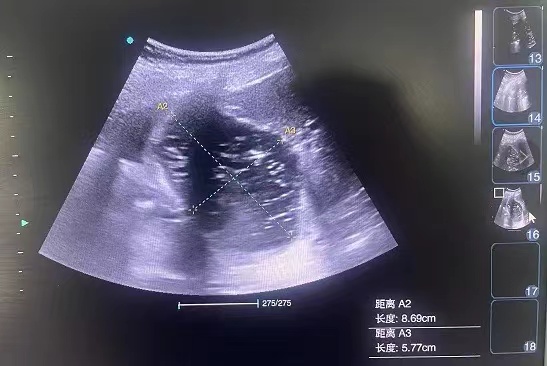

重症超声的定义:重症超声是在重症医学理论指导下,运用超声技术,针对重症患者,以问题为导向的、多目标整合的动态评估过程,是确定重症治疗,尤其是血流动力学治疗方向及调整精细治疗的重要手段。

(4)在评估腹部器官功能方面也表现出色。可以检查肝脏、脾脏、肾脏等器官的形态和血流情况,及时发现腹腔内出血、脏器损伤或梗阻等异常,避免病情的延误。